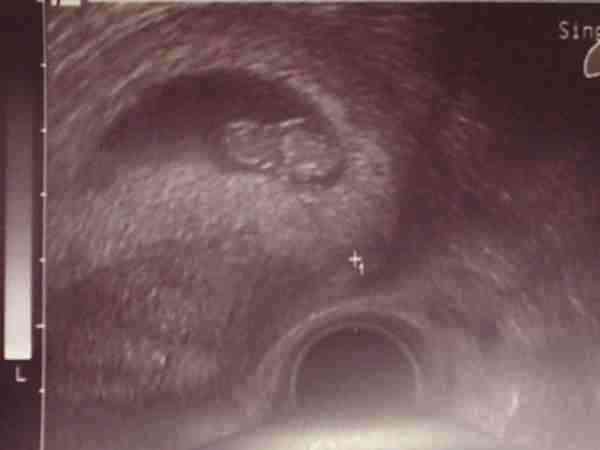

csütörtökön, azaz 3-án voltam újra ultrahangon. a leletem szerint CRL 8mm, azaz gondolom, hogy már ilyen "nagy", 1 embrió és jó szívműködés... ja, és grav.s. 6, úgyhogy ebből azt vettem le, hogy 6 hetes a baba, vagyis 8 hetes terhes vagyok. sajnos pontos adatokat még nem tudok, mert a ciklusom hossza nagyon változó, úgyhogy nem tudom, hogy pontosan melyik napon lehetett a fogamzás.